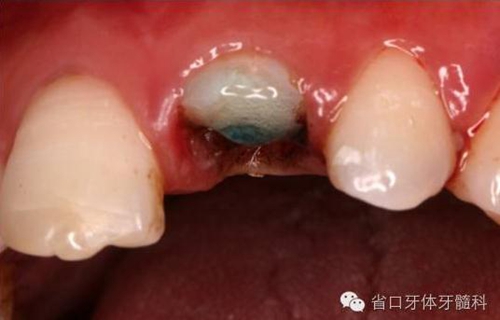

圖9. 腭側(cè)電刀切齦止血、暴露斷面,殘根斷面磷酸酸蝕

圖10. 11. 斷冠磷酸酸蝕處理

圖12. 超聲蕩洗纖維樁道

圖13. 纖維樁及斷冠粘接固定